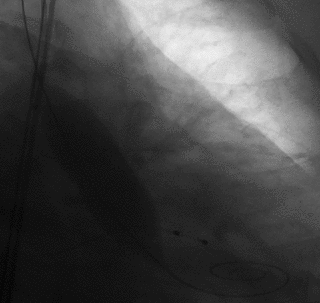

策略制定

陈灏教授团队总结了该病例特点:三叶瓣,纯返流,瓣环周长68mm,LVOT周长70.9mm,LCA/RCA分别高15/9mm,STJ最大直径29.8mm,考虑纯返流病例,瓣膜锚定难度大,术中或术后可能出现瓣膜移位等严重并发症,瓣膜的精准定位和稳定释放极为关键。经反复评估,考虑VitaFlow Liberty可回收电动输送系统可以实现快速稳定且精准的释放、回收及瓣膜锚定,且瓣膜的双层裙边设计在减少瓣周漏的同时增加锚定摩擦力。oversize选择VitaFlow27瓣膜。

术中操作

顺畅过弓

瓣膜开始释放